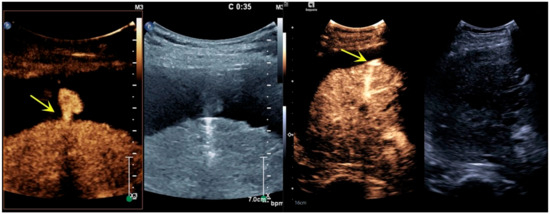

3.1. Imaging Features

3.2. Treatment Effect